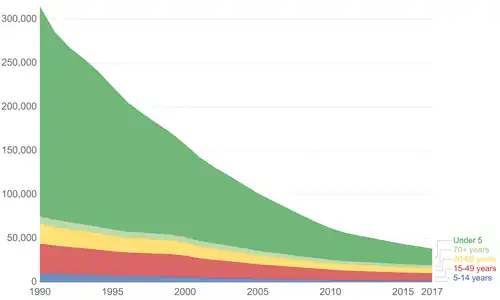

Tetanus deaths between 1990 and 2017 by age group.[57]

Tetanus deaths between 1990 and 2017 by age group.[57]

Tetanus occurs in all parts of the world but is most frequent in hot and wet climates where the soil has a high organic content.[1] In 2015, there were about 209,000 infections and about 59,000 deaths globally.[6][7] This is down from 356,000 deaths in 1990.[8] In the US, there are about 30 cases per year, almost all of which were in people who had not been vaccinated.[9] An early description of the disease was made by Hippocrates in the 5th century BC. The cause of the disease was determined in 1884 by Antonio Carle and Giorgio Rattone at the University of Turin, and a vaccine was developed in 1924.[1]

In 2013, it caused about 59,000 deaths—down from 356,000 in 1990.[8] Tetanus, notably the neonatal form, remains a significant public health problem in non-industrialized countries, with 59,000 newborns dying worldwide in 2008 as a result of neonatal tetanus.[55][56] In the United States, from 2000 through 2007, an average of 31 cases were reported per year.[1] Nearly all of the cases in the United States occur in unimmunized individuals, or individuals who have allowed their inoculations to lapse.[1]